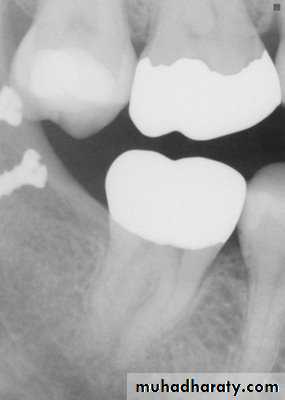

Dental materials. This radiograph shows several metallic and non-metallic dental materials. Since all of the metal restorations are equally radiopaque, their size and shape is observed to determine the type of material. The materials present in this radiograph are: (1) amalgam;(2) porcelain-fused-to-metal crown; (3) post and core; (4) gutta percha; (5) base material; (6) full metal crown, which is the posterior abutment of a three-unit bridge; (7) retention pin; and (8) metal pontic (part of the three-unit bridge).